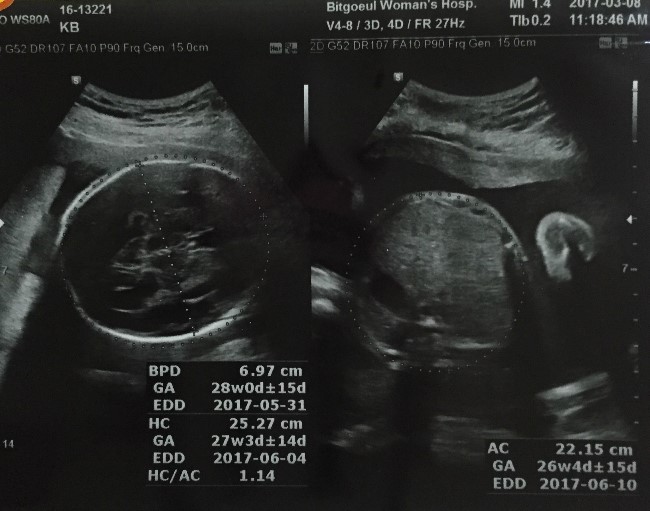

임신 26주 입체 초음파, 당뇨 검사했어요 & 임신 7개월(24~27주) 증상 및 관리

2017. 02. 17. 임신 7개월에 진입! 임신 24주 김대중 컨벤션 센터 KBC 맘앤 베이비페어...